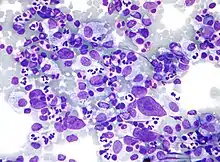

| Micrograph showing a large B cell lymphoma. Field stain. | |